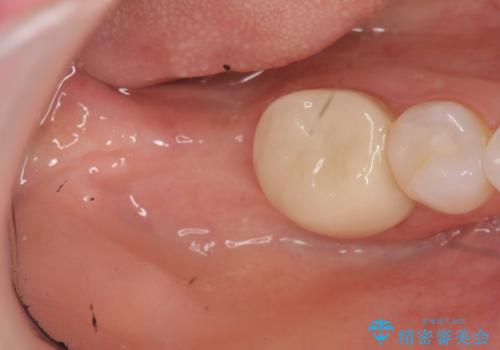

奥歯のインプラント治療

- 右下の奥歯を虫歯で喪失しそれ以来よく物が噛めず、改善を求めて来院されました。

入れ歯かインプラント治療のご提案を行い、よりしっかりとかめるインプラント治療を希望されました。

骨との結合する期間が早く、大きな咬合力にもしっかりと耐えることのできるストローマンインプラントを用いた咬合機能回復を計画します。

- 44万円(ストローマンインプラント・チタンカスタムアバットメント・仮歯・フルジルコニアクラウン)費用は治療当時の料金となります